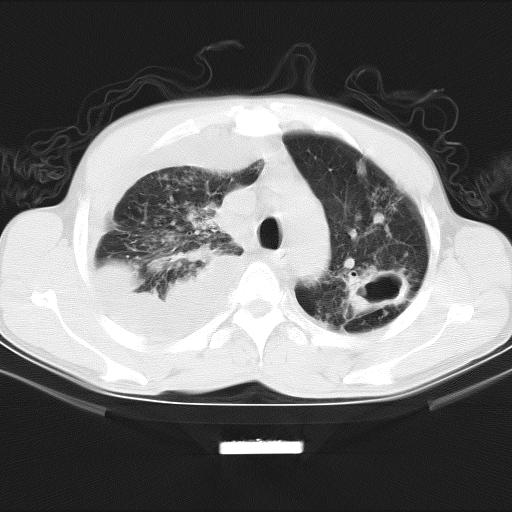

男性,44岁,结核病史多年。现胸闷气短,咳嗽,偶咳血。

1、右侧大量胸腔积液伴右肺压缩性膨胀不全,建议抽液治疗后复查 2、两肺继发性tb伴空洞形成。

1)两肺继发性肺结核伴空洞形成,左肺多发性结核球。2)右侧大量胸腔积液伴右肺部分膨胀不全。3)纵隔淋巴结肿大。

吉大一院胸水抽检结果:结核性胸水

结核性胸水——结核性胸膜炎 感谢楼主反馈结果